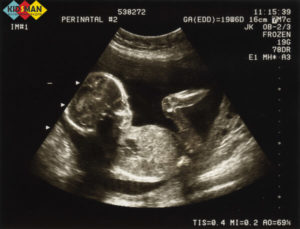

На УЗИ отчетливо виден малыш. Он шевелит ручками и ножками, иногда поворачивает лицо к аппарату. Так родители могут увидеть контуры личика. Обследование покажет, какую позицию он занимает и размеры плода.

На фото при проведении УЗИ мама может уже увидеть, как малютка улыбается, трет глазки и зевает, а также показывает язычок и пытается совладать с мимикой лица.

Зачастую на фото при проведении УЗИ запечатлена первая улыбка малютки и кулачок, уютно устроившийся под щечкой.Формирование нервной системы и мозга практически завершены, теперь малютка лучше владеет своим телом, он уже осознанно пытается пнуть ножкой мамин животик, пытается согнуть пальчики, а также ухватиться ими за пуповину.

Глаза маленького человечка полностью сформированы и он уже может открывать глазки, а также наблюдать розоватое свечение сквозь стенки плаценты, некоторым мамам при проведении УЗИ кажется, что малыш на них смотрит, этот момент можно даже запечатлеть на фото. Он слышит мамин голос, реагирует на резкие звуки извне, а также уже с легкостью отличает ласковые интонации в голосе мамы или негативные эмоции.